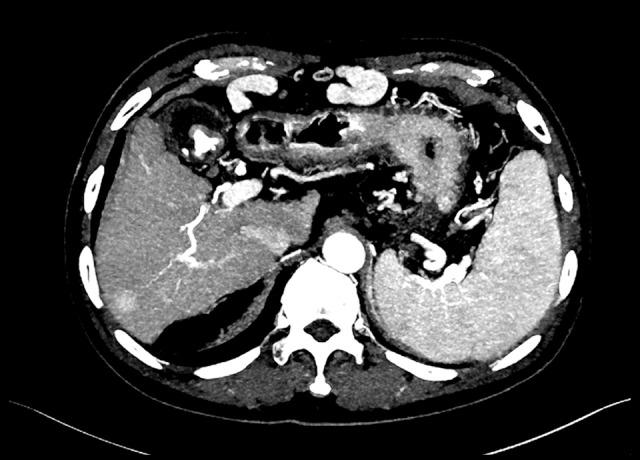

BACKGROUND The aim of this study was to investigate the feasibility of a split-bolus combined phase contrast-enhanced computed tomography protocol in evaluation of liver vasculature in hepatocellular carcinoma (HCC) patients for the purpose of surgery guidance. MATERIAL AND METHODS Two groups of patients were recruited for the study: 24 consecutive cases of HCC who underwent multiphasic CT examination, and 22 consecutive cases who afterwards underwent split-bolus combined phase CT examination. The multiphasic protocol included an unenhanced scan and 3 image acquisitions after contrast injection. The injection of contrast medium was 440 mgI/kg in a single bolus. The split-bolus combined phase protocol included unenhanced scan and combined phase. The injection of contrast medium was 440 mgI/kg for the first bolus and 220 mgI/kg for the second bolus. The vascular delineation was evaluated with Likert scales. The CT values were measured, and the contrast-to-noise ratio (CNR) was calculated. We also compared the effective radiation dose (ED) of the 2 protocols. RESULTS All mean CT values were significantly higher in the split-bolus protocol than in the multiphasic protocol (all P.05). The ED was significantly lower in the split-bolus protocol, corresponding to a dose reduction of 66% compared to the multiphasic protocol (P<.05). The scores of the branches of the hepatic vein in the split-bolus protocol were not lower than those in the multiphasic protocol. CONCLUSIONS For the preoperative HCC patients, the split-bolus combined phase CT examination meets the diagnostic requirement of surgical planning, with approximately 60% reduction in the radiation dose.

材料与方法 本研究招募了两组患者:连续24例接受多期CT检查的HCC患者,以及随后连续22例接受团注分割联合相位CT检查的患者。多期扫描方案包括平扫及注射对比剂后的3次图像采集。对比剂以440 mgI/kg的剂量单次团注。团注分割联合相位扫描方案包括平扫及联合相位扫描。首次团注对比剂的剂量为440 mgI/kg,第二次为220 mgI/kg。采用Likert量表评估血管的显示情况。测量CT值并计算对比噪声比(CNR)。我们还比较了两种扫描方案的有效辐射剂量(ED)。

结果 团注分割扫描方案的所有平均CT值均显著高于多期扫描方案(所有P<0.05)。团注分割扫描方案的ED显著更低,与多期扫描方案相比剂量降低了66%(P<0.05)。团注分割扫描方案中肝静脉分支的评分不低于多期扫描方案。

结论 对于术前HCC患者,团注分割联合相位CT检查满足手术规划的诊断要求,且辐射剂量降低约60%。